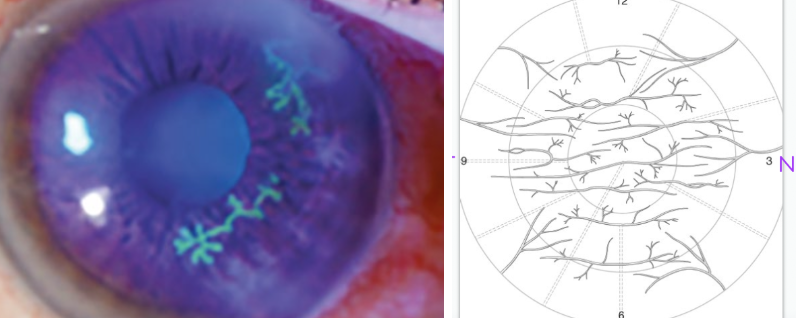

Vortical keratopathy is a condition where the corneal epithelium develops pigmented or deposit lines in a swirl (vortex) pattern. Which conditions can cause vortical (swirl) pigmented deposits in the cornea?

Metabolic diseases: Fabry’s disease

Medications: Amiodarone

Which viruses can cause dendriform corneal lesions, and what is their pattern?

Neurotropic viruses - Herpes Simplex Virus (HSV)

form a branching (tree-like) pattern, visible with staining

branching b/c corneal nerves themselves have a branching innervation

Why are corneal nerve fibers difficult to see clinically?

Corneal nerve fibers entering from limbus demyelinate when they pass through the Bowman’s layer → hard to see